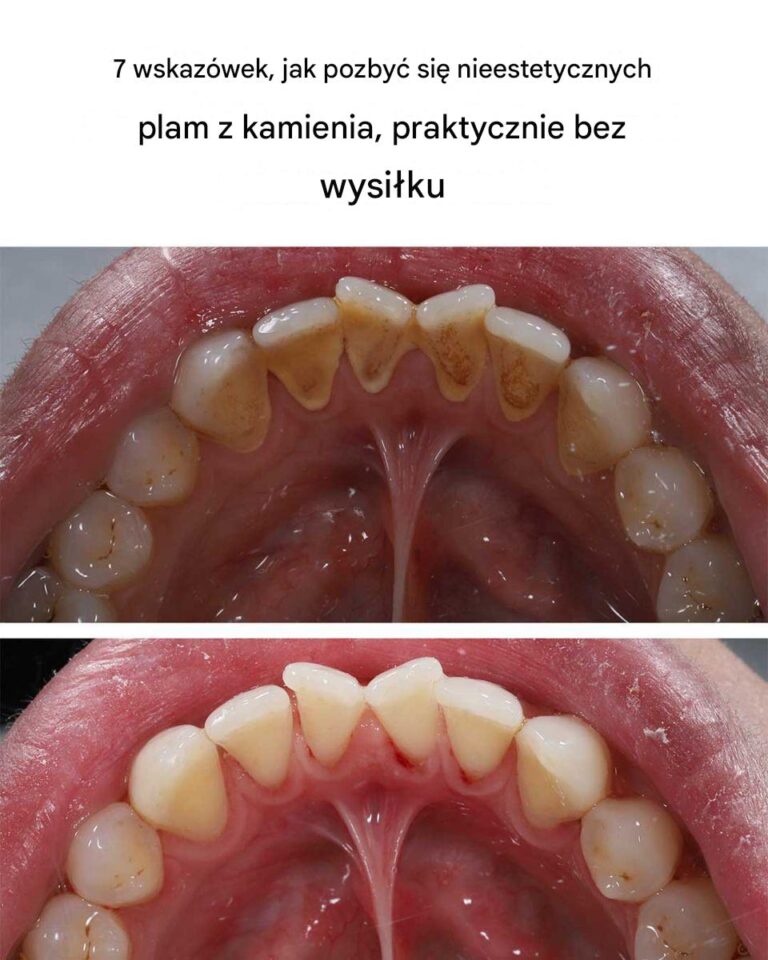

7 wskazówek, jak pozbyć się nieestetycznych plam z kamienia, praktycznie bez wysiłku

Kamień nazębny, zwany również kamieniem nazębnym, to stwardniała forma płytki nazębnej, która może tworzyć się na zębach i pod dziąsłami. Powstaje w wyniku gromadzenia…